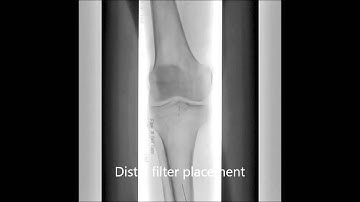

JetStream Atherectomy for In-Stent Restenotic Lesion